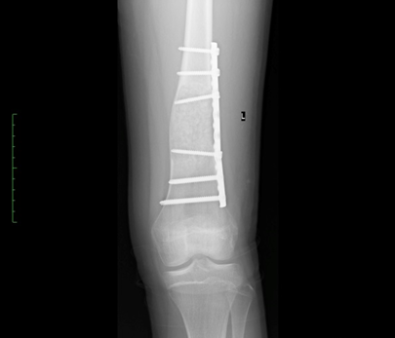

• A simple or an aneurismal bone cyst. Typically presents with a pathological fracture (a fracture with no significant injury) or pain. The treatment varies according to the diagnosis, symptoms and location.

Post-operative xray of a distal aneurysmal bone cyst treated with curettage, grafting and plating.